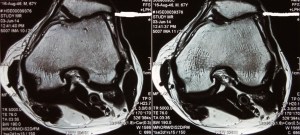

An MRI scan of his left knee showed a root tear of the posterior horn of his medial meniscus with loss of hoop stress, extrusion of the medial meniscus together with subchondral oedema of the medial tibial-femoral compartment and thinning of the cartilage of the medial compartment of his left knee.

In addition, the osteoarthritis of the kneecap compartment was also seen.

The MRI also confirmed that the lateral knee compartment was healthy and that the central cruciate ligaments were intact.